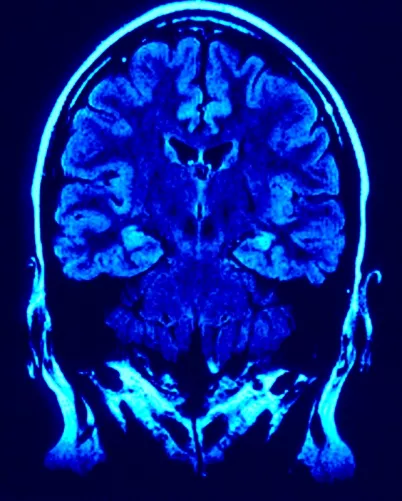

Az agy frontalis metszete képalkotó eszközzel